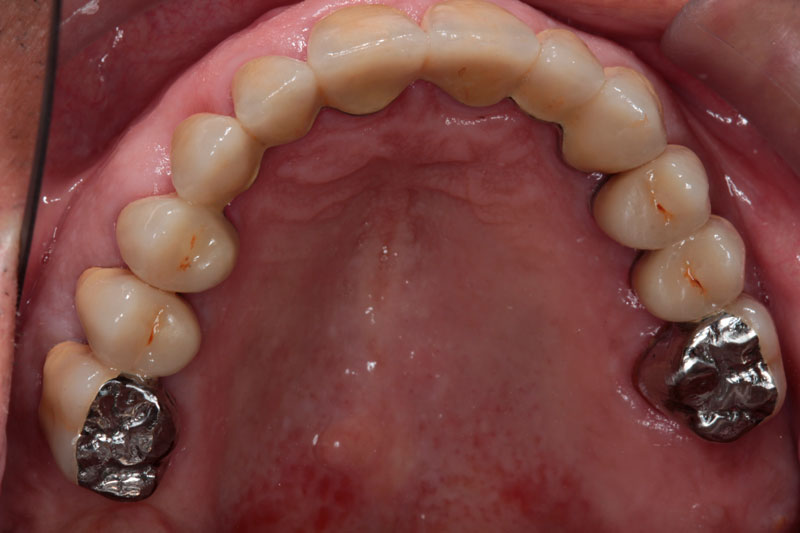

Después